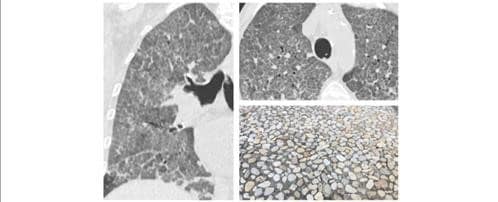

- What is “Crazy Paving” and what does it have to do with COVID? Crazy paving refers to the appearance of ground-glass opacity with superimposed interlobular septal thickening and intralobular septal thickening, seen on chest High Resolution CT. It is a non-specific finding that can be seen in a number of conditions. Here are two CT scan views showing this pattern, along with a picture of a mosaic paved pathway that inspired this whimsical radiological description.

Crazy paving: not exactly a yellow brick road, but I’ll say goodbye for now.